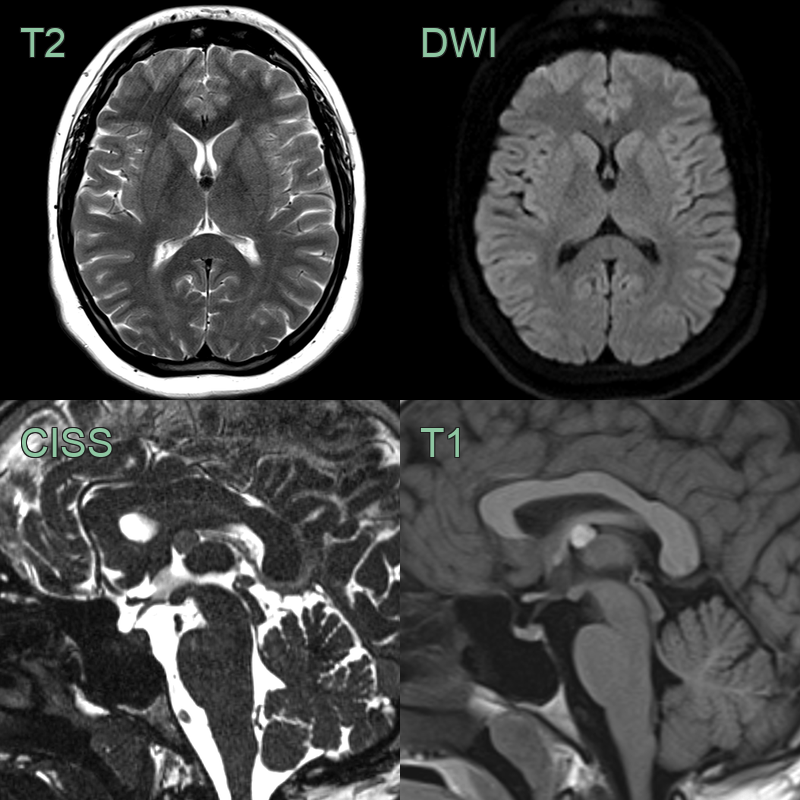

- MRI findings:

- T1-weighted: Variable signal intensity (hyperintense to CSF)

- T2-weighted: Usually hypointense to CSF

- FLAIR: Hyperintense signal

- Contrast enhancement: Typically minimal or absent

- DWI: No restricted diffusion

| Epidermoid cyst | Diffusion restriction on DWI, irregular margins |